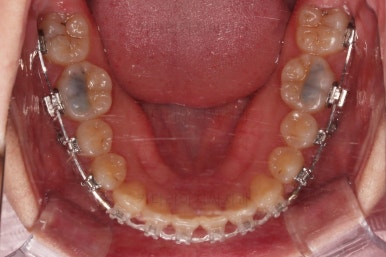

사용한 장치 : 자가결찰 세라믹(엠파워 클리어, Empower clear) + 미니스크류

입 안을 보면 밑에 치열이나 다른 부분은 비교적 양호한데 유달리 윗니 송곳니만 위치가 좋지 못하네요.

이번에 사용한 장치는 엠파워 클리어라고 하는 자가결찰 세라믹 장치인데요.

철사를 잡아주는 뚜껑이 브라켓에 달려있어 스스로(자가) 철사를 잡을 수 있는(결찰) 장치라는 뜻인데요. 대표적으로는 클리피씨라고 하는 장치가 있습니다. 클리피는 일본장치, 엠파워는 미국장치라는 차이점만 있고 큰 틀에선느 동일한 장치라고 볼 수 있습니다.

충치가 곳곳에 보이는데요.

성인들은 충치가 멈춰있는 정지우식일 가능성도 있으며 크기가 현재 크지 않고 향후 변화되지 않는다면 그대로 두기도 합니다.

이번 환자분도 교정치료에 방해되는 부분이나 급해보이는 추료만 우선 진행하고 교정 중에 충치가 커지는지 증상이 생기는지 관찰해 보기로 했습니다.

연산동교정치과 교정장치 부착 직후의 모습입니다.